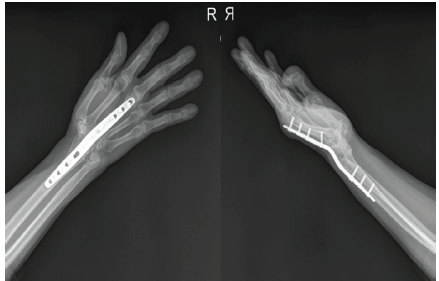

Postoperatively, antibiotic therapy was administered according to culture results in consultation with the infectious diseases department. After approximately a 3-month interval, definitive arthrodesis was performed (Figure 3).

Figure 3: The second stage of the two-stage surgery consisted of wrist arthrodesis using plate-and-screw fixation.

Through a dorsal incision between the third and fourth extensor compartments, the spacer was removed, and an autologous bone graft harvested from the iliac crest was placed. Stable fixation was achieved using an arthrodesis plate in an appropriate functional position.